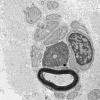

PERIPHERAL NEUROPATHY

1 NORMAL NERVE ANATOMY